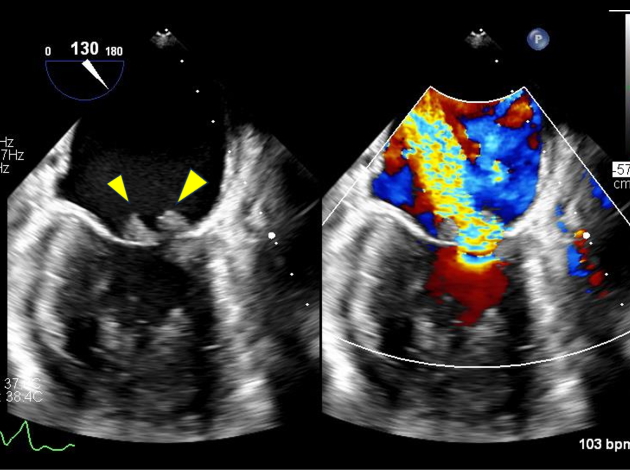

僧帽弁逸脱症(僧帽弁後尖の逸脱)